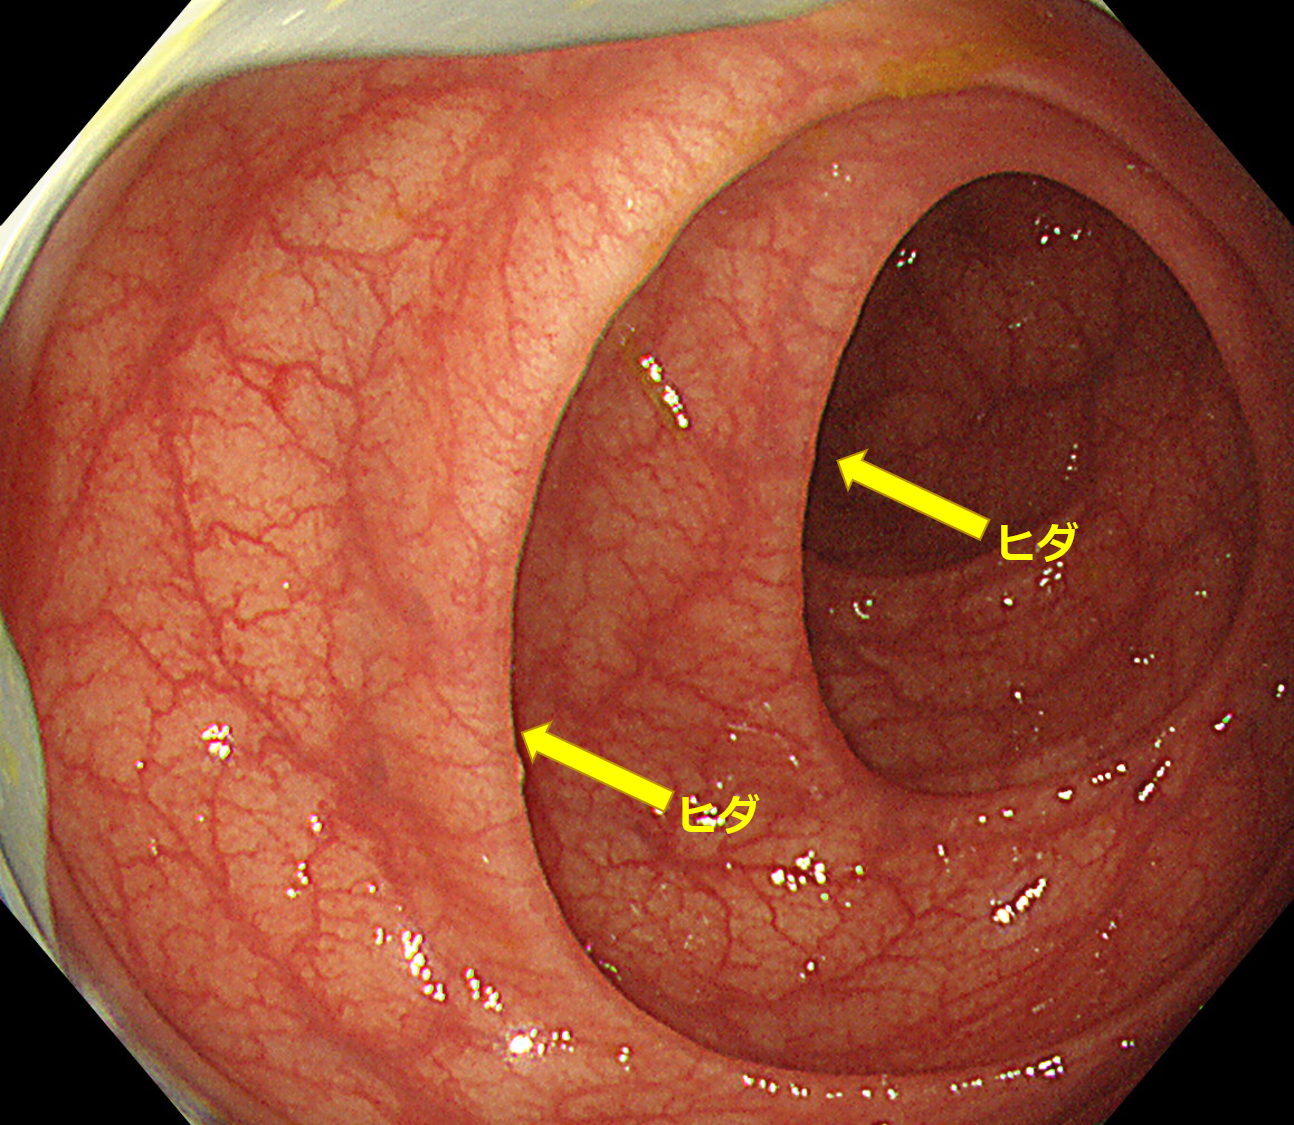

大腸内は普段しぼんだ風船のようになっています。検査中にはヒダとヒダの間までしっかり観察するために空気を注入します。この空気は検査後に抜くことができません。便がつまった便秘ではありませんが空気が詰まった便秘の状態となるためお腹の張りや吐き気などを訴える方がいるわけです。

大腸という臓器は内腔にヒダが多く存在します。カメラで観察すると長いトンネルにふすまがたくさんあるように見えます。このヒダは中途半端に開いたふすまのようなっています。内視鏡は前方はよく見えますが真横などは死角となるため、このふすまの裏にあるポリープは見逃されがちです。

先端フードは図のようにカメラの先端に装着します。帽子の”つば”のようにヒダをめくるように観察が可能になります。

装着すると…

写真のようになります。